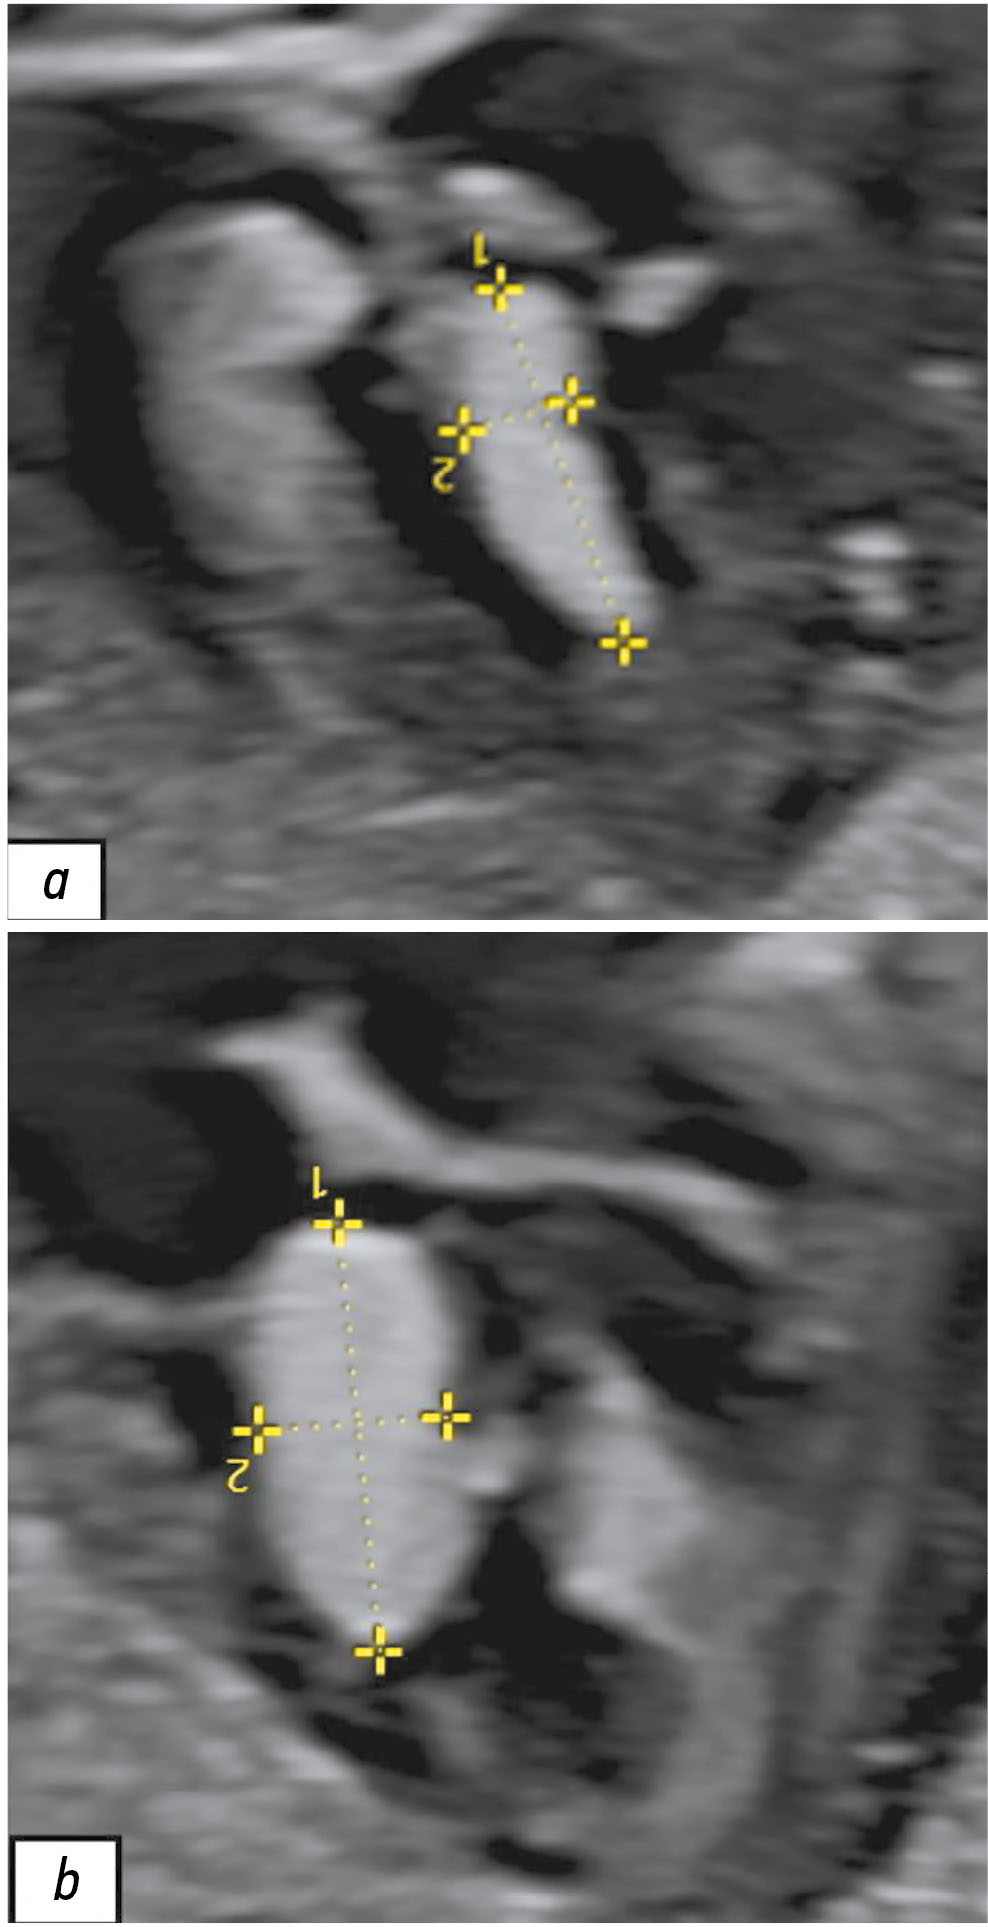

Hypophysitis is a rare inflammatory disorder that affects the pituitary gland and infundibulum, stems from autoimmune, infiltrative, infectious, or unknown causes. Its clinical diagnosis can be challenging because several pituitary lesions, including adenomas and metastases, may clinically present with similar characteristics. Magnetic resonance imaging is crucial for diagnosing suspected cases of hypophysitis and categorizing them as adenohypophysitis (anterior pituitary gland involvement) or infundibulo-neurohypophysitis (pituitary stalk and posterior pituitary involvement). Hypophysitis can be categorized as primary (autoimmune) or secondary due to local lesions (e.g., granulomas, cysts, adenomas) or systemic diseases (e.g., sarcoidosis, Wegener’s granulomatosis). Different factors may have impact on clinical course of hypophysitis. Among them background treatment. These cases have not been sufficiently studied and are practically not presented in publications.

A 37-year-old female with a history of hyperprolactinemia was being treated symptomatically with cabergoline. At first magnetic resonance imaging heterogeneity of the hypophysis was revealed. In September 2021 the follow-up magnetic resonance imaging revealed an increase in the size and heterogeneity of the pituitary gland. In December 2021, the patient developed severe COVID-19-associated pneumonia and was treated with corticosteroids and oxygen support. In May 2022 magnetic resonance imaging revealed a marked increase in the size and heterogeneity of the pituitary gland. Significant clinical and radiological improvement were stated after adding prednisone (10 mg in the morning and 5 mg in the evening) to her treatment.

The patient was followed-up during the COVID-19 pandemic. The management and imaging studies of such patients may be tricky due to the effects related to COVID-19 and its treatment.

During monitoring of hypophysitis, physicians should consider the impact of COVID-19 treatment, particularly corticosteroid therapy, when evaluating the radiological changes.